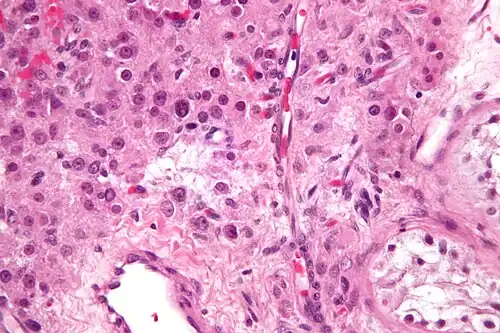

| Histopathology of a Leydig cell tumor, high magnification, H&E stain, showing typical features.[1] | |

A conclusive diagnosis is made via histology, as part of a pathology report made during or after surgery. Reinke crystals are classically found in these tumours and help confirm the diagnosis, although they are seen in less than half of all Leydig cell tumours. Immunohistochemical markers of Leydig cell tumours include inhibin-alpha, calretinin, and melan-A.[9]

High magnification micrograph of a Leydig cell tumour. H&E stain.

High magnification micrograph of a Leydig cell tumour. H&E stain. -